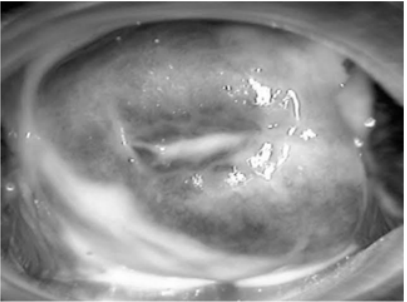

Uma gestante com dezesseis semanas e quatro dias compareceu ao pronto-atendimento com queixa de “corrimento vaginal” há quatro dias. O teste das aminas foi positivo e o exame especular é ilustrado na figura 1. Após a realização de coloração Gram, o resultado pode ser observado na figura 2.

Figura 1